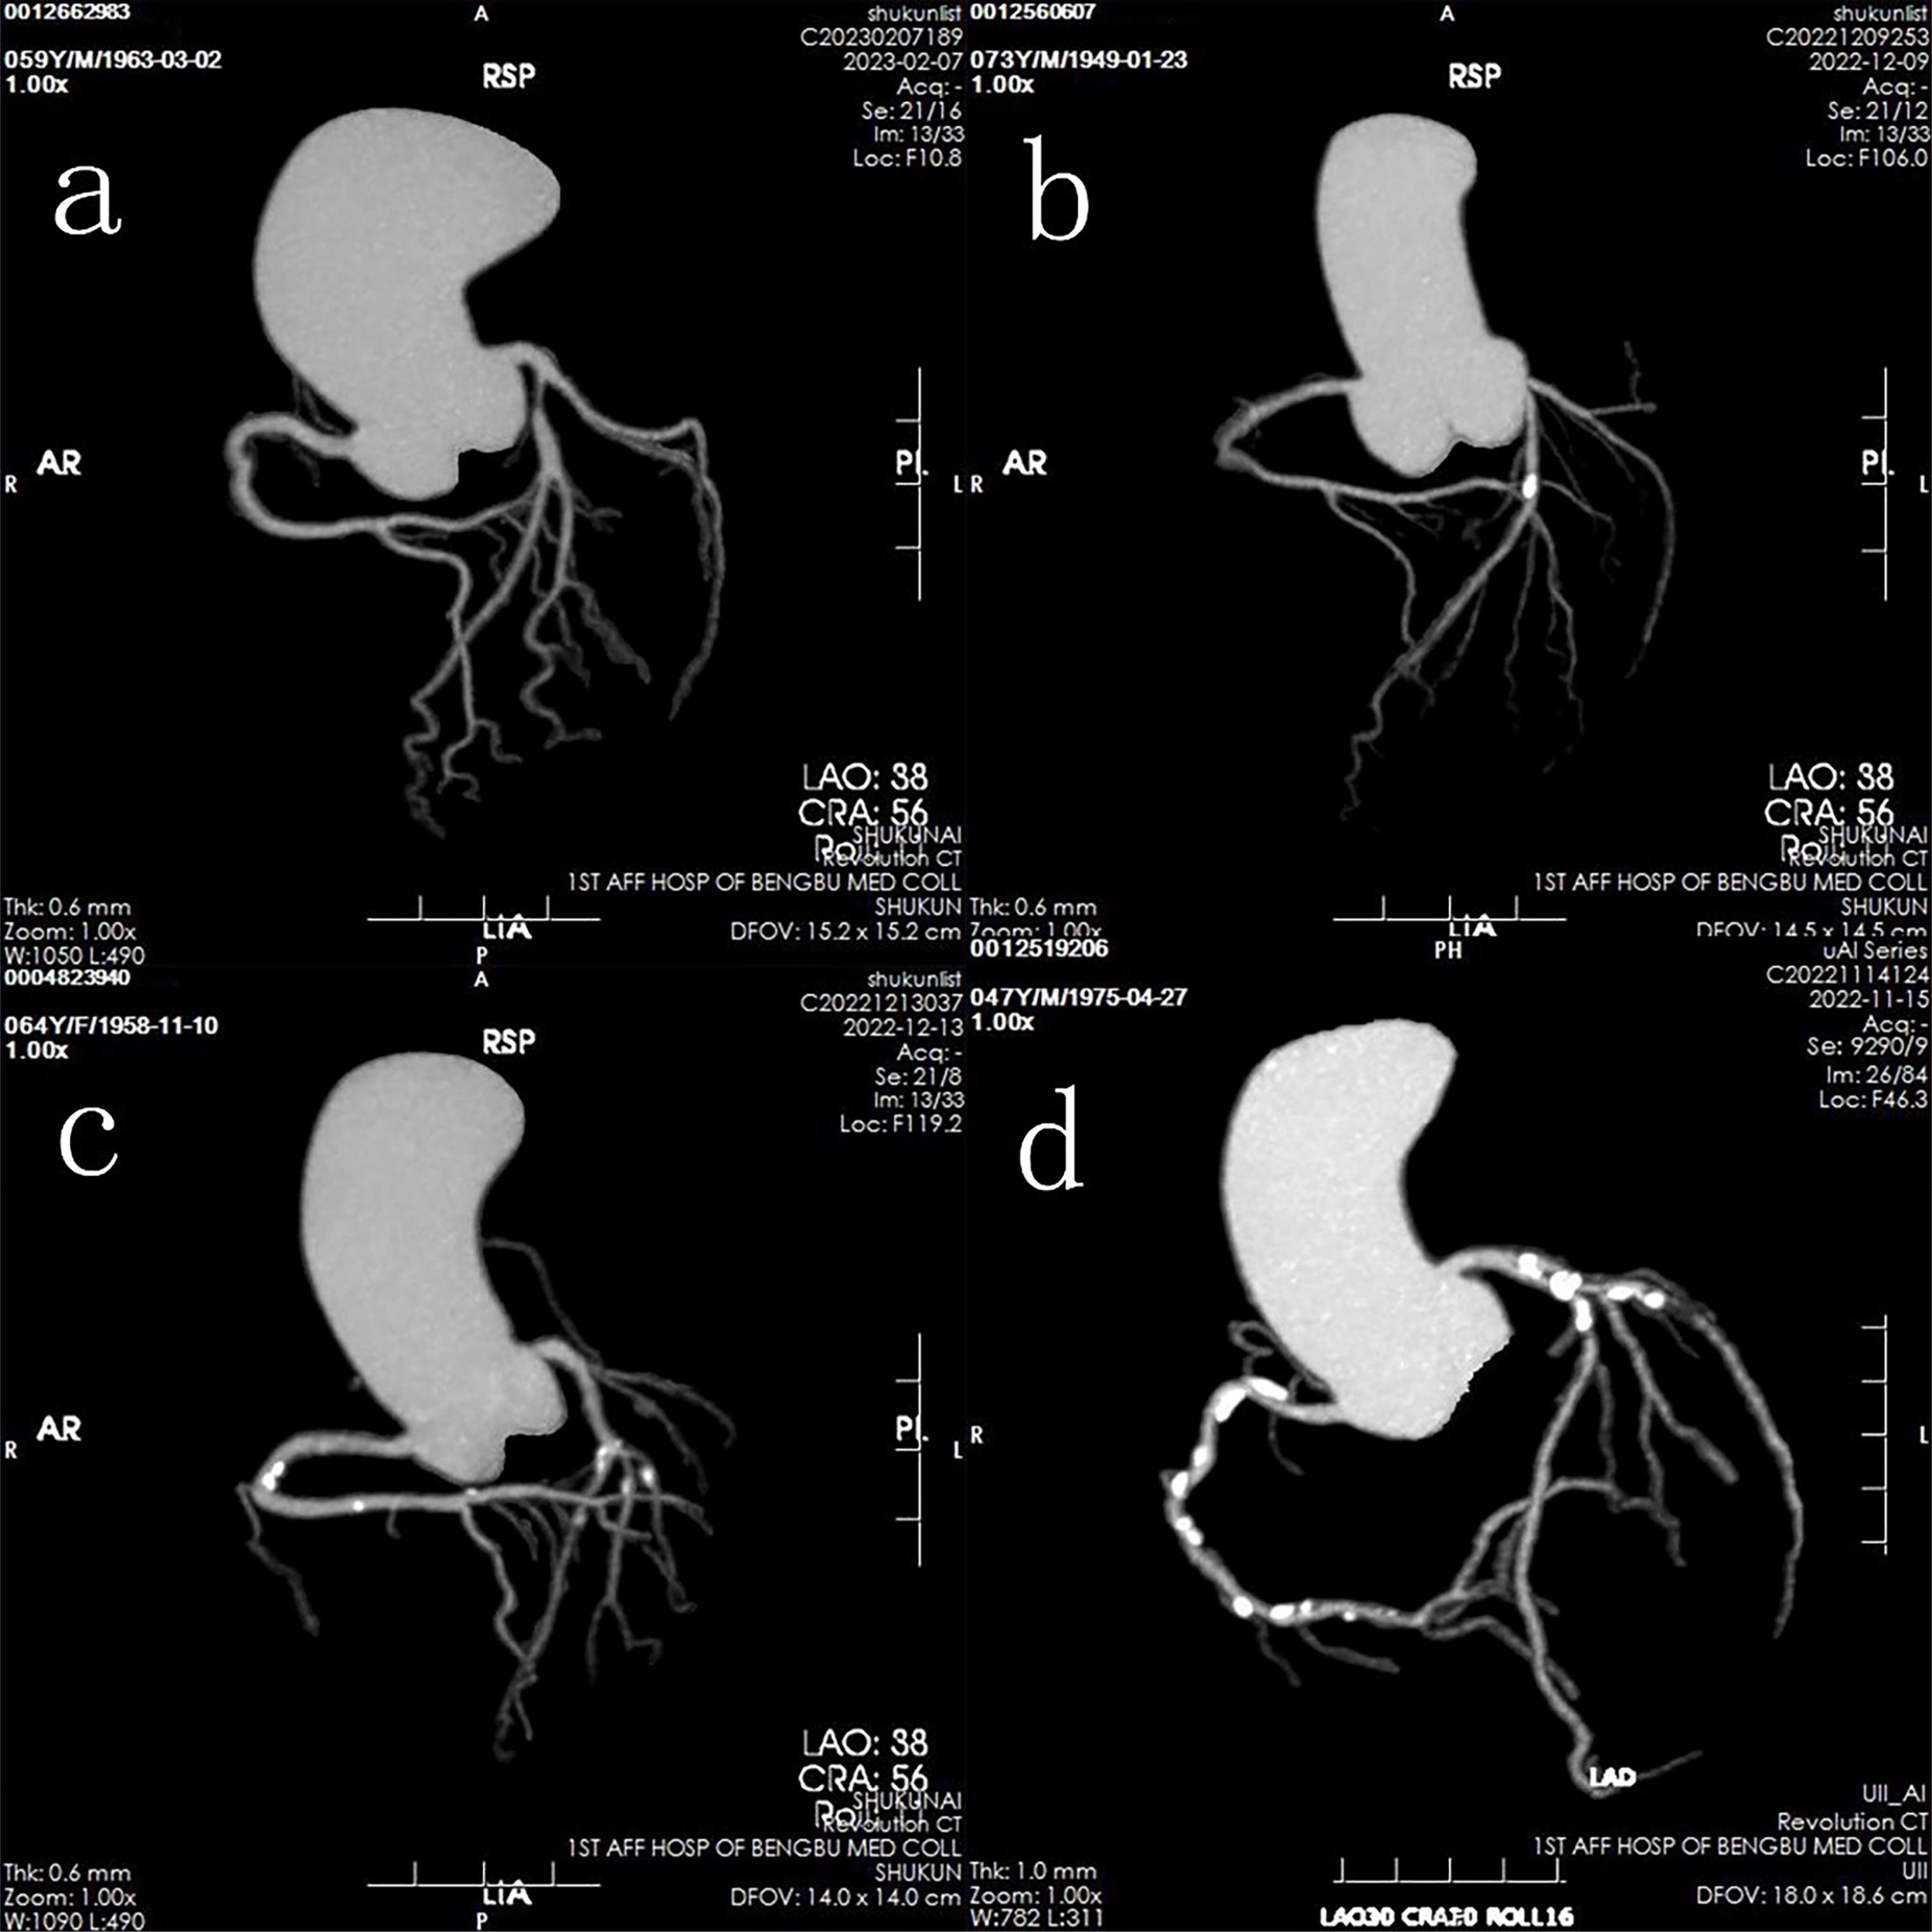

Patients were classified into two primary groups: a normal group (CACS = 0) and a calcification group (CACS > 0). The calcification group was further subdivided into three categories based on CACS severity: mild calcification (0 < CACS < 100), moderate calcification (100 ≤ CACS < 400), and severe calcification (CACS ≥ 400) (Figure 1).

Figure 1

Representative images of four groups based on calcification levels: (a) Normal group; (b) Mild calcification group; (c) Moderate calcification group; (d) Severe calcification group.